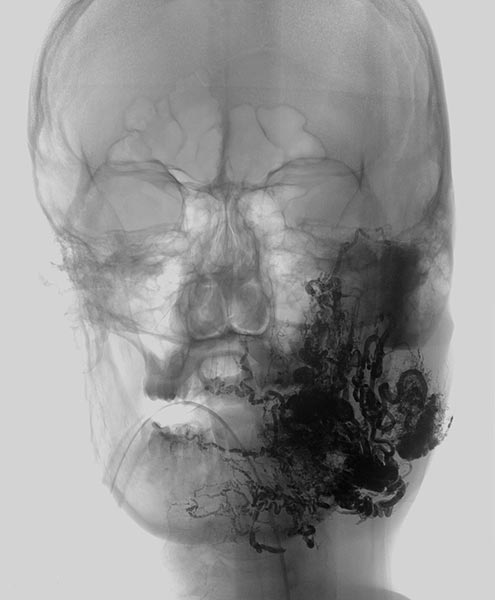

Complete filling of the entire nidus of the AVM using ethylene-vinyl alcohol copolymer (EVOH). This is visible in the radiograph shown here (AP) as a black, reticular radiopaque cast specimen within the occluded AVM vessels.